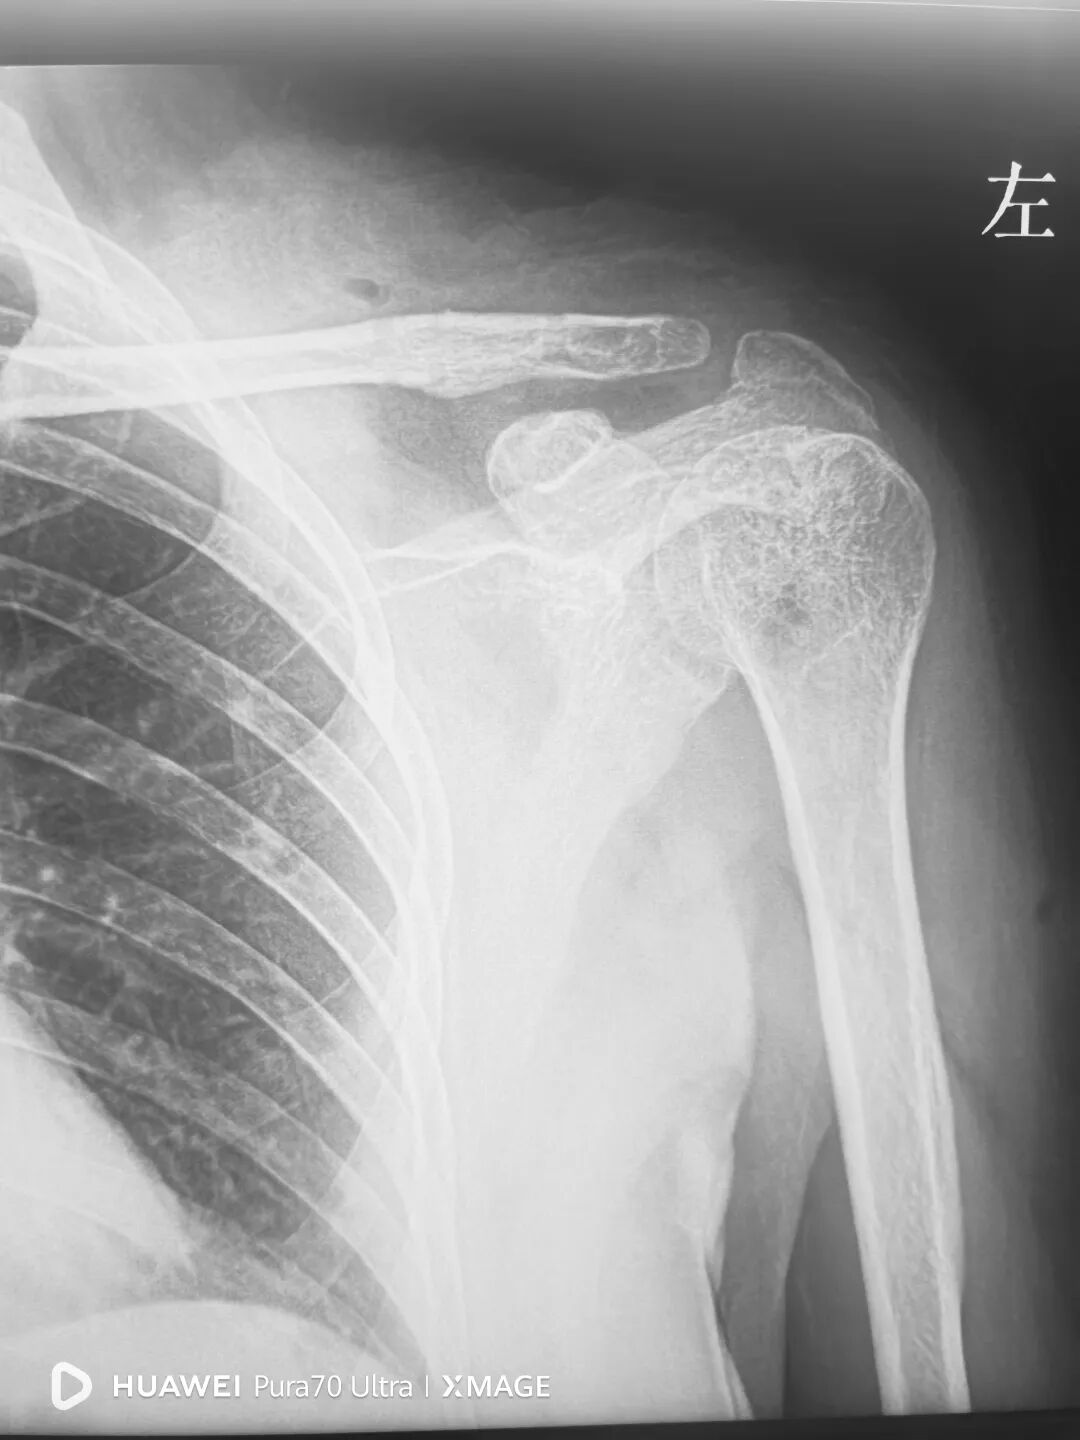

病例一:

钩弧度和深度不合适,肩峰骨溶解